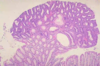

What is this?

UC -> continuous - no skip lesions

What will histology show in UC?

confined to mucosa and inflammtory infiltrate